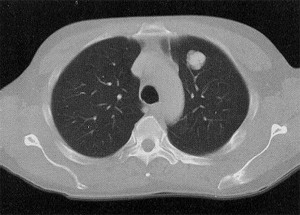

A single CT slice at the level of the aortic arch demonstrates a lobulated, 3-cm left upper lobe adenocarcinoma